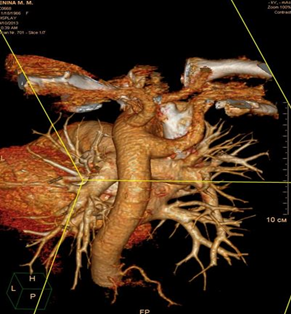

В послеоперационном периоде проводились дополнительные исследования – по данным ангиографии и компьютерной томографии подтверждено наличие сосудистой аномалии в виде a. lusoria. Послеоперационный период у больной протекал гладко, без осложнений. Фонация голосовых связок не была изменена. Проведенные дополнительные исследования подтвердили наличия a. lusoria. По данным МСКТ-ангиографии правая подключичная артерия (a. lusoria) отходит отдельным стволом позади и левее от места отхождения левой подключичной артерии, расположение ее предпозвоночное позади пищевода, отмечается сдавление пищевода (рис. 6 а, б, в).

Рис. 6. Результаты рентгенологического исследования: а – МСКТ расположения a. lusoria; б – компьютерная ангиография (вид спереди); в – компьютерная ангиография (вид сзади).

По данным ангиографии – ангиографическая картина a. lusoria. Справа налево от дуги аорты отходят устья правой и левой общих сонных артерий, левой подключичной артерии и правой подключичной артерии (последние два практически на одном уровне) (рис. 7).

Рис. 7. Ангиография.